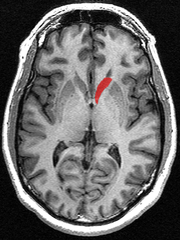

Caudate nucleus

The caudate nucleus is one of the structures that make up the dorsal striatum, which is a component of the basal ganglia.[1] While the caudate nucleus has long been associated with motor processes due to its role in Parkinson's disease,[2] it plays important roles in various other nonmotor functions as well, including procedural learning,[3] associative learning and inhibitory control of action, [4] among other functions. The caudate is also one of the brain structures which compose the reward system and functions as part of the cortico–basal ganglia–thalamic loop.[1]

The caudate nuclei are located near the center of the brain, sitting astride the thalamus. There is a caudate nucleus within each hemisphere of the brain. Individually, they resemble a C-shape structure with a wider "head" (caput in Latin) at the front, tapering to a "body" (corpus) and a "tail" (cauda). Sometimes a part of the caudate nucleus is referred to as the "knee" (genu).[5]